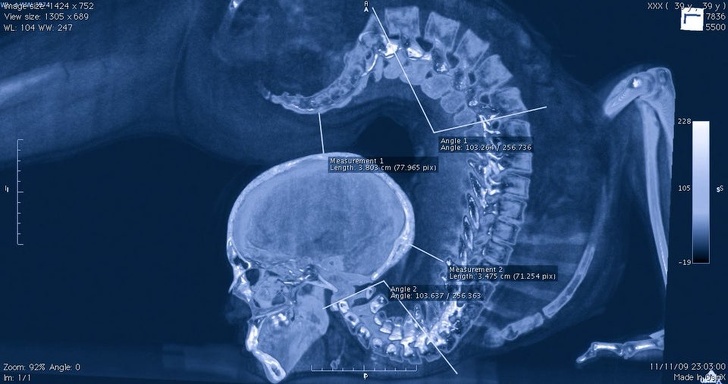

正在进行体操运动的体操运动员,在CT下的状态。